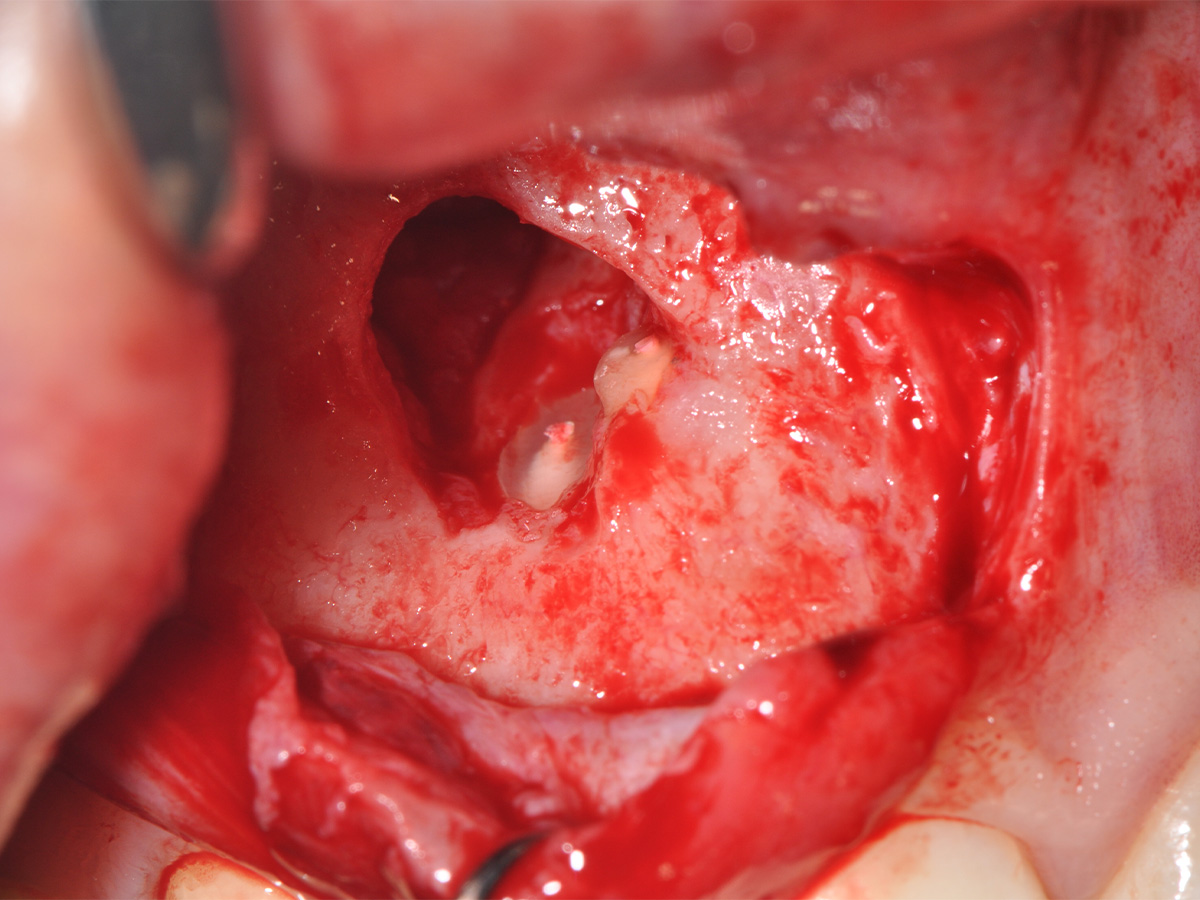

Abbildung 11

Anschließend erfolgte eine Wurzelspitzenresektion an den Zähnen 11 und 12 durch die vestibuläre ossäre Perforation, gefolgt von einer ultraschallbasierten, retrograden Kanalaufbereitung und Abdichtung mit MTA.

Mit der Patientin wurde der Versuch des Zahnerhaltes trotz ausgedehnter Zyste besprochen. Gleichzeitig sollte das Zystenlumen zu einer sicheren ossären Durchbauung geführt werden, um eine implantologische Sofortversorgung vorzubereiten, falls zu einem späteren Zeitpunkt eine Zahnentfernung notwendig werden sollte. In der Phase vor der geplanten Operation wurden die Wurzelkanalfüllungen an Zahn 11 und 12 durch einen Endodontologen alio loco revidiert. Die Schnittführung wurde aufgrund des bestehenden „Gummy Smile“ hoch im Vestibulum geführt – so konnte die delikate Parodontalstruktur in ihrer Form unangetastet belassen werden, um einen möglichst optimalen ästhetischen Erfolg zu erreichen (Abb. 8, 9). Nach vestibulärer Freilegung wurde die Zyste vollständig entfernt und zur histopathologischen Untersuchung eingesandt (Abb. 10). Anschließend erfolgte eine Wurzelspitzenresektion an den Zähnen 11 und 12 durch die vestibuläre ossäre Perforation (Abb. 11), gefolgt von einer ultraschallbasierten, retrograden Kanalaufbereitung und Abdichtung mit MTA. Um die knöcherne Durchbauung am Boden der Zyste osteoinduktiv zu unterstützen, wurden mit Hilfe eines mechanischen Knochenschabers aus dem Bereich des rechten naso-palatinalen Pfeilers Knochenchips entnommen und als erste basale Augmentationsschicht in den ossären Defekt eingebracht (Abb. 12). Der größere Anteil von 80 % des Defektvolumens wurde mit einem vollständig resorbierbaren, xenogenen Augmentationsmaterial aufgefüllt (Abb. 13) (mp3®, OsteoBiol®). Der Defekt wurde zum Vestibulum hin mit einer stabilen, vollständig degradierbaren Membran abgedeckt (Abb. 14) (Soft Cortical Lamina, OsteoBiol®). Zum einen wurde hiermit im Sinne der GBR das Weichgewebe vom Augmentat getrennt. Zum anderen verhinderte die stabile Membran das Einwachsen eines Weichgewebeankers in den Defekt und damit eine narbige Verziehung im Vestibulum. Um eine Verschiebung der Membran zu vermeiden, wurde diese mit zwei Titanpins in der Kortikalis fixiert. Die Pins wurden bei Beschwerdefreiheit in situ belassen (Titan-Bone-Pin-System). Der Wundverschluss erfolgte einschichtig mit nicht resorbierbarem Nahtmaterial (Abb. 15) (Seralene® 5-0 DS-15). Peri- und postoperativ wurde eine antibiotische Abschirmung unter Fortführung für insgesamt drei Tage mit Amoxiclav 875/125 1-0-1 durchgeführt.